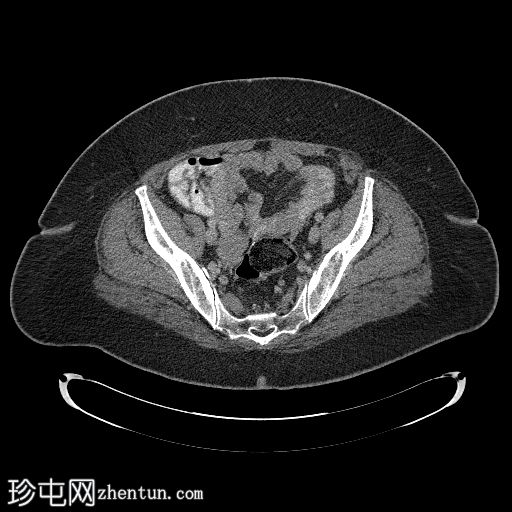

轴位T1加权像

增强脂肪抑制像